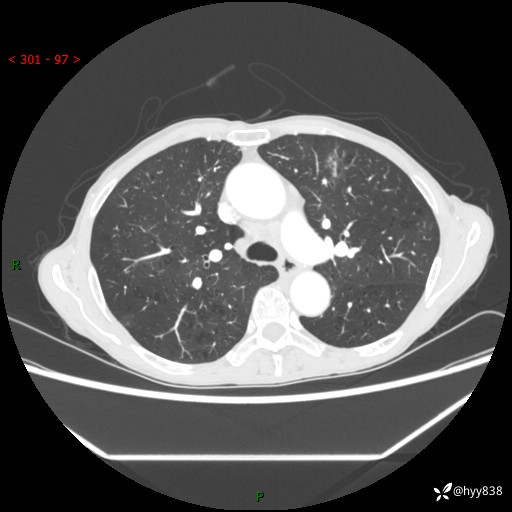

69岁/女,发现肺占位3天余。精彩好病例,请慧诊---(有结果)

【患者信息】:69岁/女

【主诉】:发现肺占位3天余

【现病史及既往史】:患者3天余前因既往肺气肿复查胸部CT发现“右肺下叶结节、双肺多发结节、双肺门及纵膈淋巴结增大”,平素偶有咳白色粘液痰,下肢乏力,无明显低热、盗汗、咯血、胸痛、喘气等不适,今为求明显结节性质遂来我院门诊就诊,门诊以“孤立性肺结节”收治入院。 起病以来,患者精神饮食睡眠一般,大小便正常,体力无明细变化,体重近年来较前下降。

【检查】:胸部CT增强